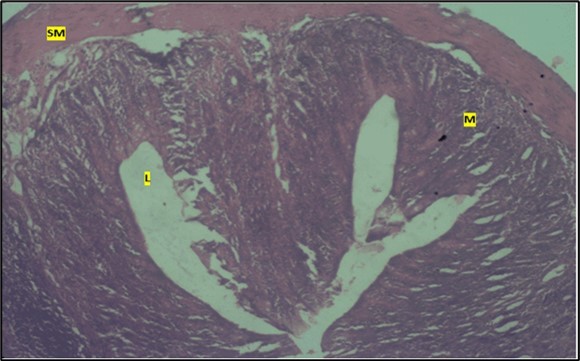

Micrographs of The Small Intestine

Histological examination of the small intestine result in control animals revealed a normal architecture with the red pulp and white pulp with no pathological observation Figure 2. Administration of Abelmoschus esculentus at low dose shows an increased cellularity with numerous cells in the Mucosa and the villi projecting towards the lumen. Focal metaplasia of mucosal cells alongside villous disruption was also observed (Figure 3). The high dose group showed normal cellular architecture with no villous disruption (Figure 4).

Figure 2.Control showing the mucosa with intestinal villi (v) projecting towards the lumen (l) and the underlying smooth muscle layer (sm) all appearing normal

Figure 3.Low dose showing numerous epithelial cells in the mucosa (m) with villi projecting towards the lumen (l). The is focal metaplasia of the mucosal cells with villous disruption. smooth muscle layer appears normal. H & E. X40

Figure 4.High dose showing a normal mucosa (m) with villi (v) projecting towards the lumen(l) and underlying smooth muscle layer (sm). No pathology seen